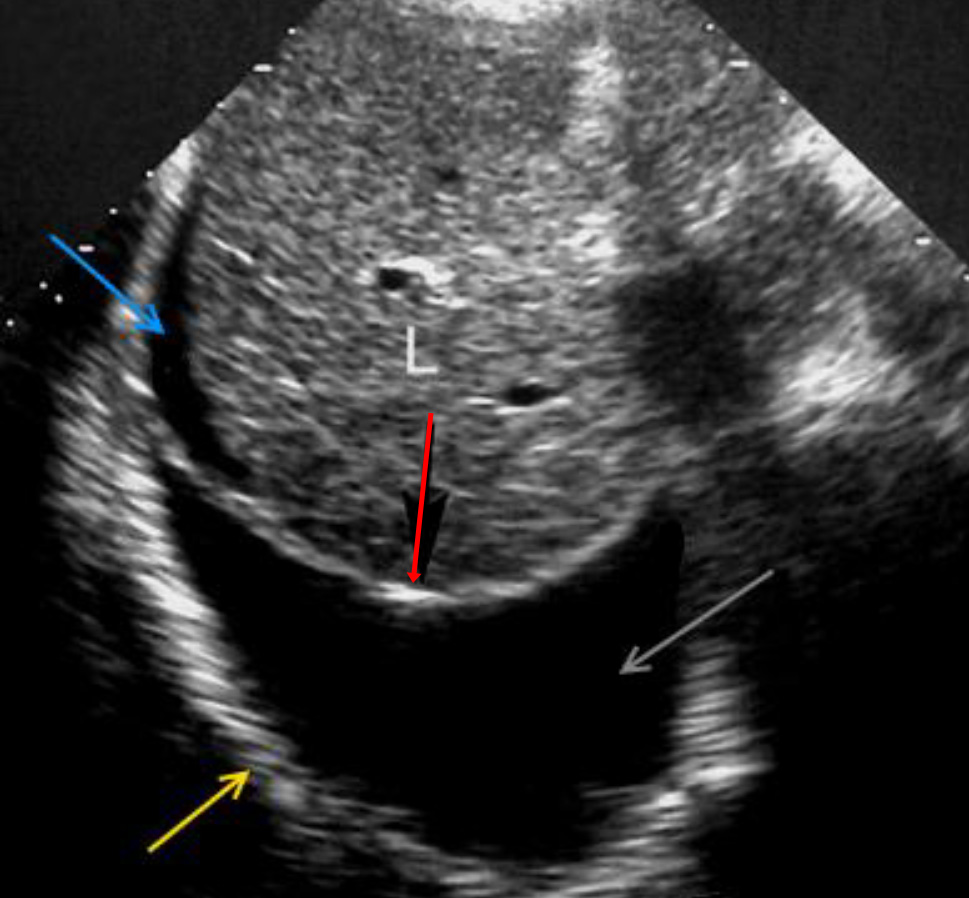

Как выглядит доля Риделя на УЗИ печени